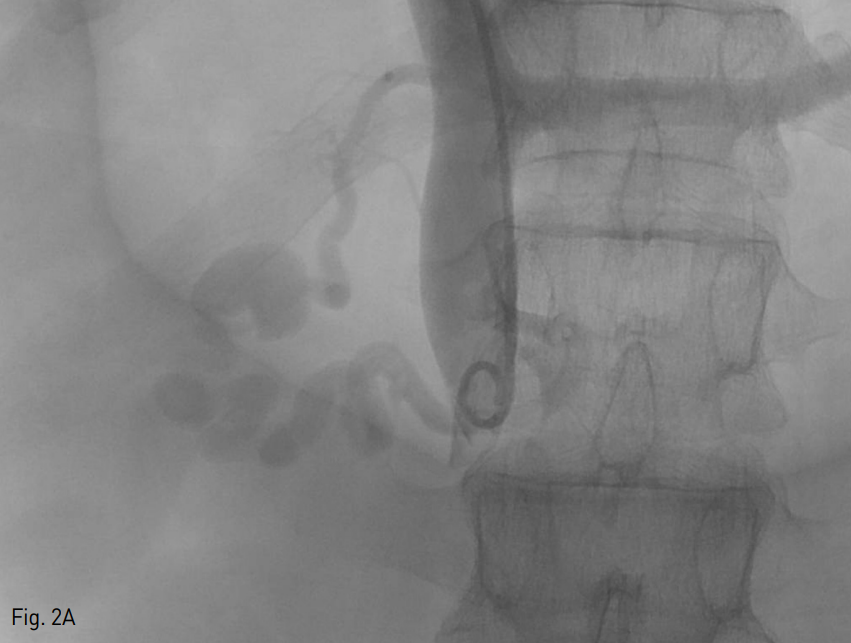

Fig. 2

A. Initial portogram shows duodenal varices with two feeding vessels and cystic dilatation

B. After superselection for inferior feeding vessel, portogram shows duodenal varices with portosystemic shunt, via right renal vein (black arrow).

초음파 유도하 우측 간문맥을 천자하여 5 Fr sheath (Terumo, Tokyo, Japan)를 삽입하였고, pig-tail catheter (Cook, Bloomington, USA)을 이용하여 시행한 간문맥 조영술 시행하였다. 간문맥 조영술상 최대 직경 2cm의 낭성 확장 및 두 개의 영양혈관을 가진 정맥류가 확인되었다 (Fig. 2A). 이후 5 Fr cobra catheter (Terumo, Tokyo, Japan) 및 2.2 Fr microcatheter (Progreat; Terumo, Tokyo, Japan)을 이용하여 아래쪽 영향혈관을 초선택 하였고, 시행한 조영술 상 오른쪽 신정맥을 경유하여 하부대정맥으로 배액되는 문맥전신단락 (portosyste mic shunt)도 확인되었다 (Fig. 2B).